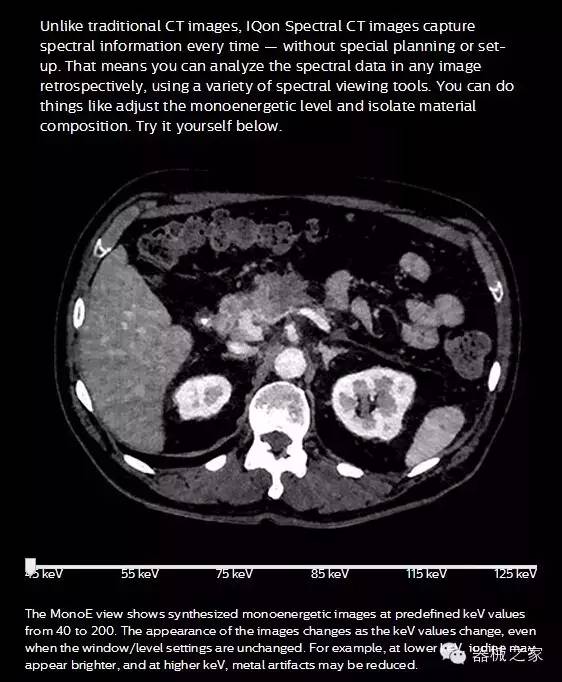

IQon光譜CT能夠按照需求提供光譜量化和工具,并能通過簡單工作流程、在低劑量下對結(jié)構(gòu)進(jìn)行定性分析

IQon光譜CT -- 是業(yè)界首臺以探測器為成像基礎(chǔ)的光譜CT,它可以在單次常規(guī)掃描下獲得傳統(tǒng)解剖影像及光譜功能影像。不僅可以提供精準(zhǔn)的診斷信息,還可簡化工作流程、在低劑量下完成定量與定性分析。